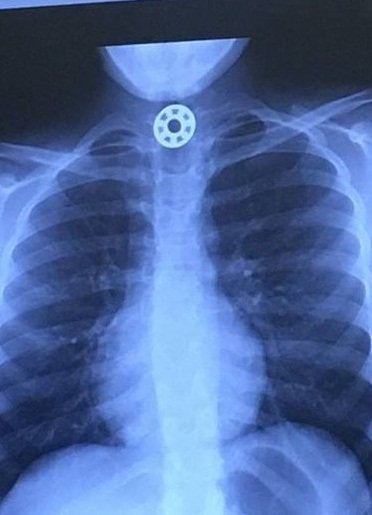

ABD'nin Houston kentinden bir kadın, kızının boğazına kaçan demir para büyüklüğündeki stres çarkının bir parçasını çıkarmak için ameliyat edilmek zorunda kalmasının ardından Facebook hesabından anne babaları uyardı.

Houston'ın hemen kuzeyinde, The Woodlands'daki Texas Çocuk Hastanesine götürülen çocuğun yutağında bilye büyüklüğünde bir şeyin sıkıştığı görüldü ve hemen ameliyat yapılması gerektiği söylendi.